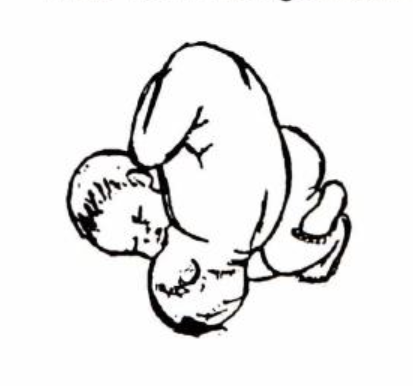

Nội xoay thai có nghĩa là xoay thai trong buồng tử cung, tiến hành khi đẻ và thường được thực hiện khi đẻ thai thứ hai của cuộc chuyển dạ sinh song thai. Nội xoay thai là kỹ thuật để chuyển ngôi thai nhi từ ngôi bất thường thành ngôi thuận để có thể sinh được bằng đường âm đạo. Chỉ định nội xoay thai khi tiên lượng sản phụ có thể sinh thường, thai nhỏ và thai nhi nằm ngang trong tử cung mẹ. Mục đích của nội xoay thai là biến ngôi thai từ ngang chuyển thành ngôi thuận để cho thuận lợi trong việc sinh thường.

Nội xoay thai là phương pháp giúp sản phụ có thể sinh thường, tránh phải thực hiện cuộc phẫu thuật lấy thai, do đó sản phụ có thời gian phục hồi nhanh hơn. Do sơ sinh đi qua ống sinh dục của người mẹ, được ống sinh dục của người mẹ co bóp lồng ngực, nên sẽ giúp trào hết dịch tiết trong phổi với phế nang.